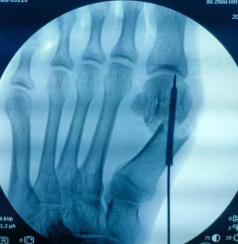

第二天,石荣剑副院长、曹广超主任、陈占斌医生手术团队为刘女士进行了微创截骨矫形内固定术。术中,松解拇内收肌及第1跖趾关节外侧关节韧带、关节囊,于第1跖趾关节近端胫侧做一长约1cm纵形切口,切除增生的拇囊,通过超声骨刀切除跖骨头骨赘、于第一跖骨颈部做关节囊外截骨,完全截断后,缩小拇外翻脚,使用螺钉固定截骨面,双足矫形仅用时1小时。术后第2天,刘女士顺利出院。

术中截骨矫形